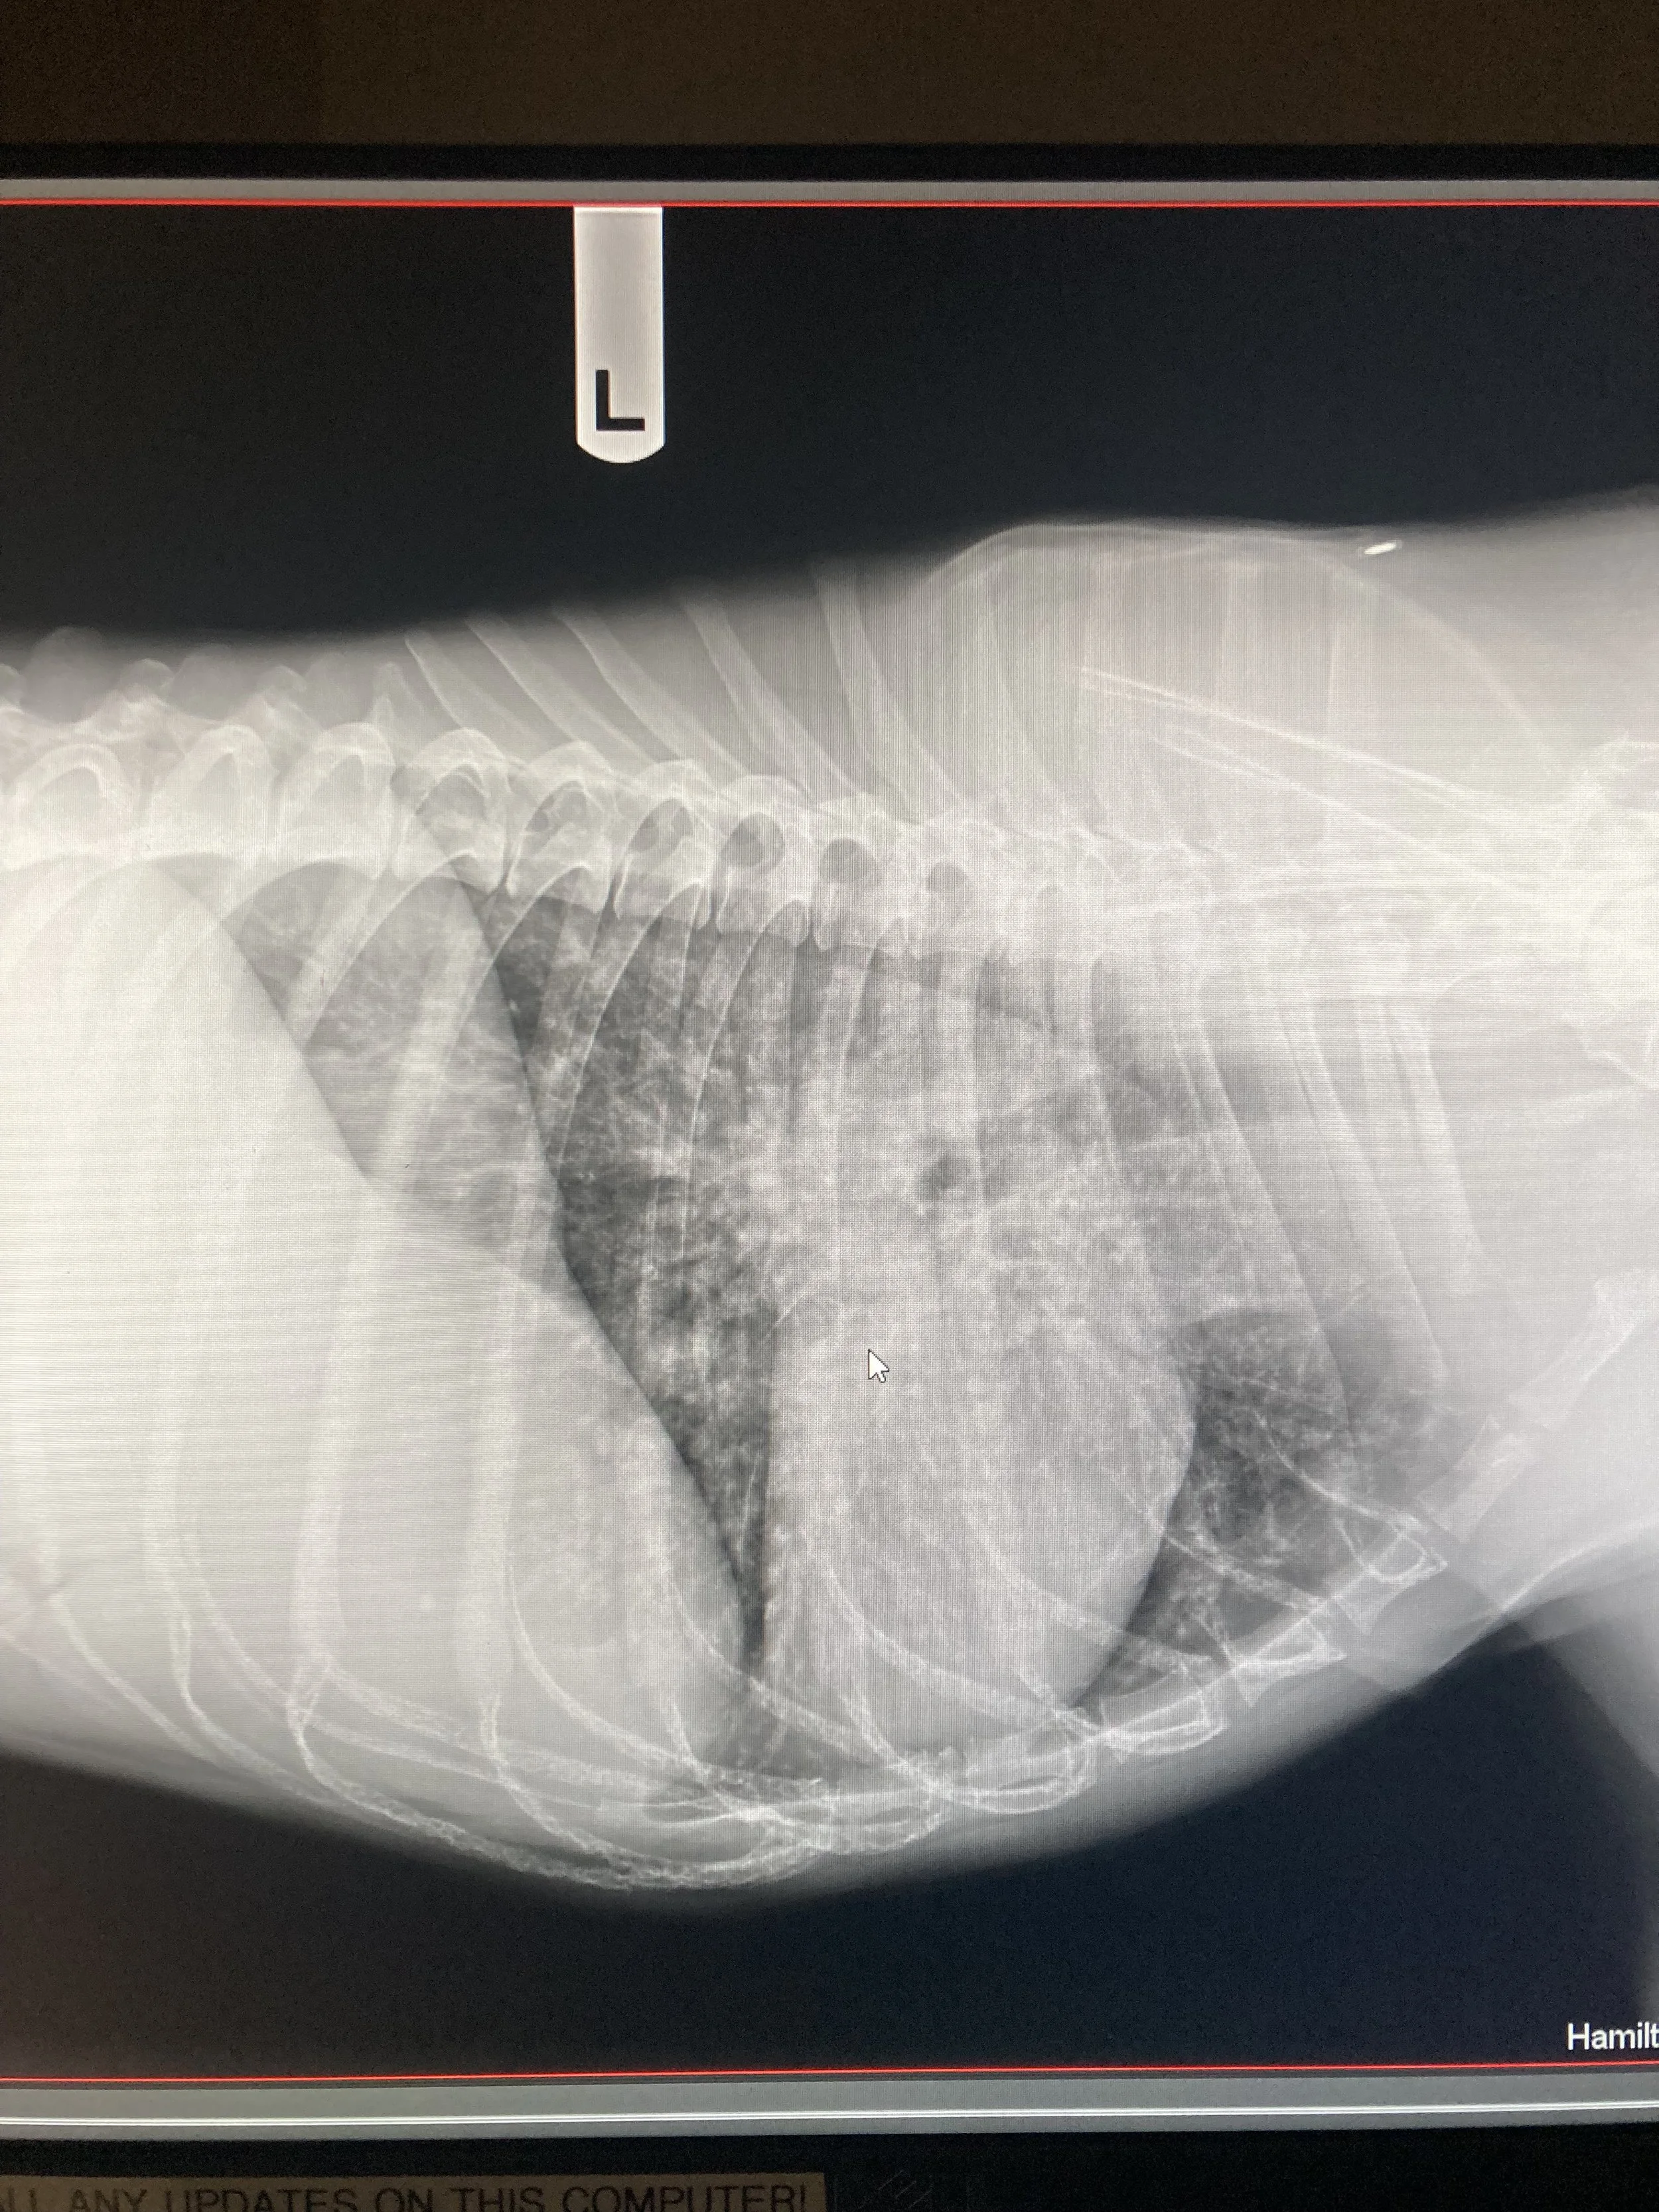

X-ray image of a dog's chest showing rib cage and lungs, labeled with the letter 'L' indicating the left side.